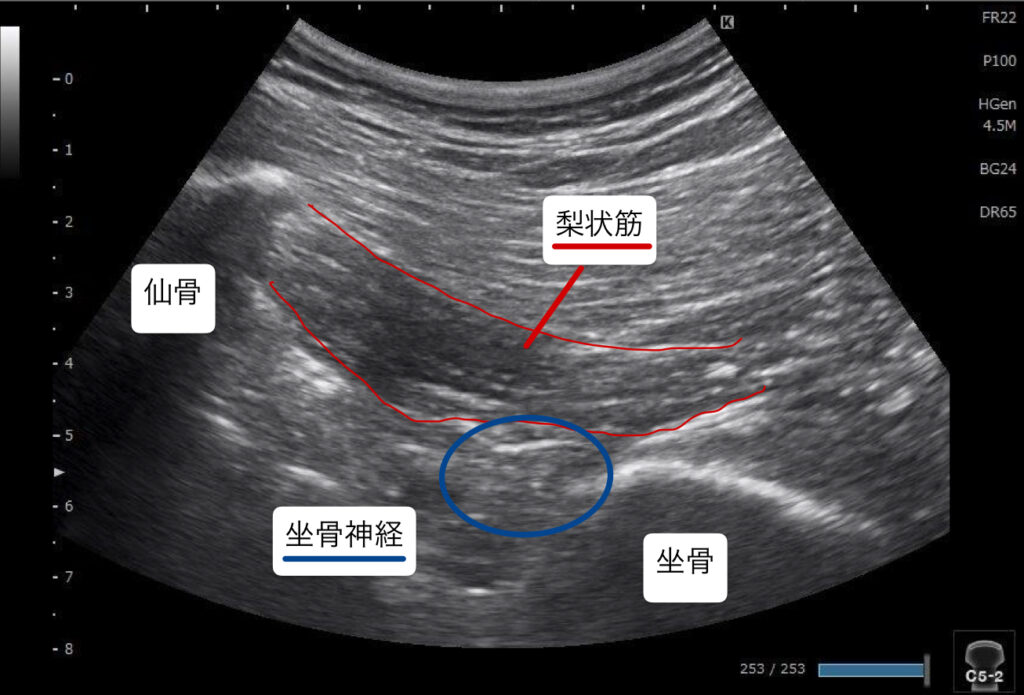

痛みが出てから1週間経過していたこともあり痛みはだいぶ軽減していた(痛み止めなどの服用なし)。痺れはまだ出ているとのことだったので理学テストと感覚障害の有無、筋力テスト、超音波エコー検査を実施。脊髄神経の圧迫による痺れの可能性は低くお尻の深層にある梨状筋という筋肉が坐骨神経と癒着(滑走低下)している可能性が考えられた。また股関節周囲の筋力の左右差は無いがかなり弱い。

臀部を中心とした手技と超音波エコー下鍼療法にて対応した。臀部の圧痛部を中心に丁寧にアプローチを行い超音波エコーで梨状筋周囲での坐骨神経の滑走低下を確認したので鍼通電を行い改善を図った。